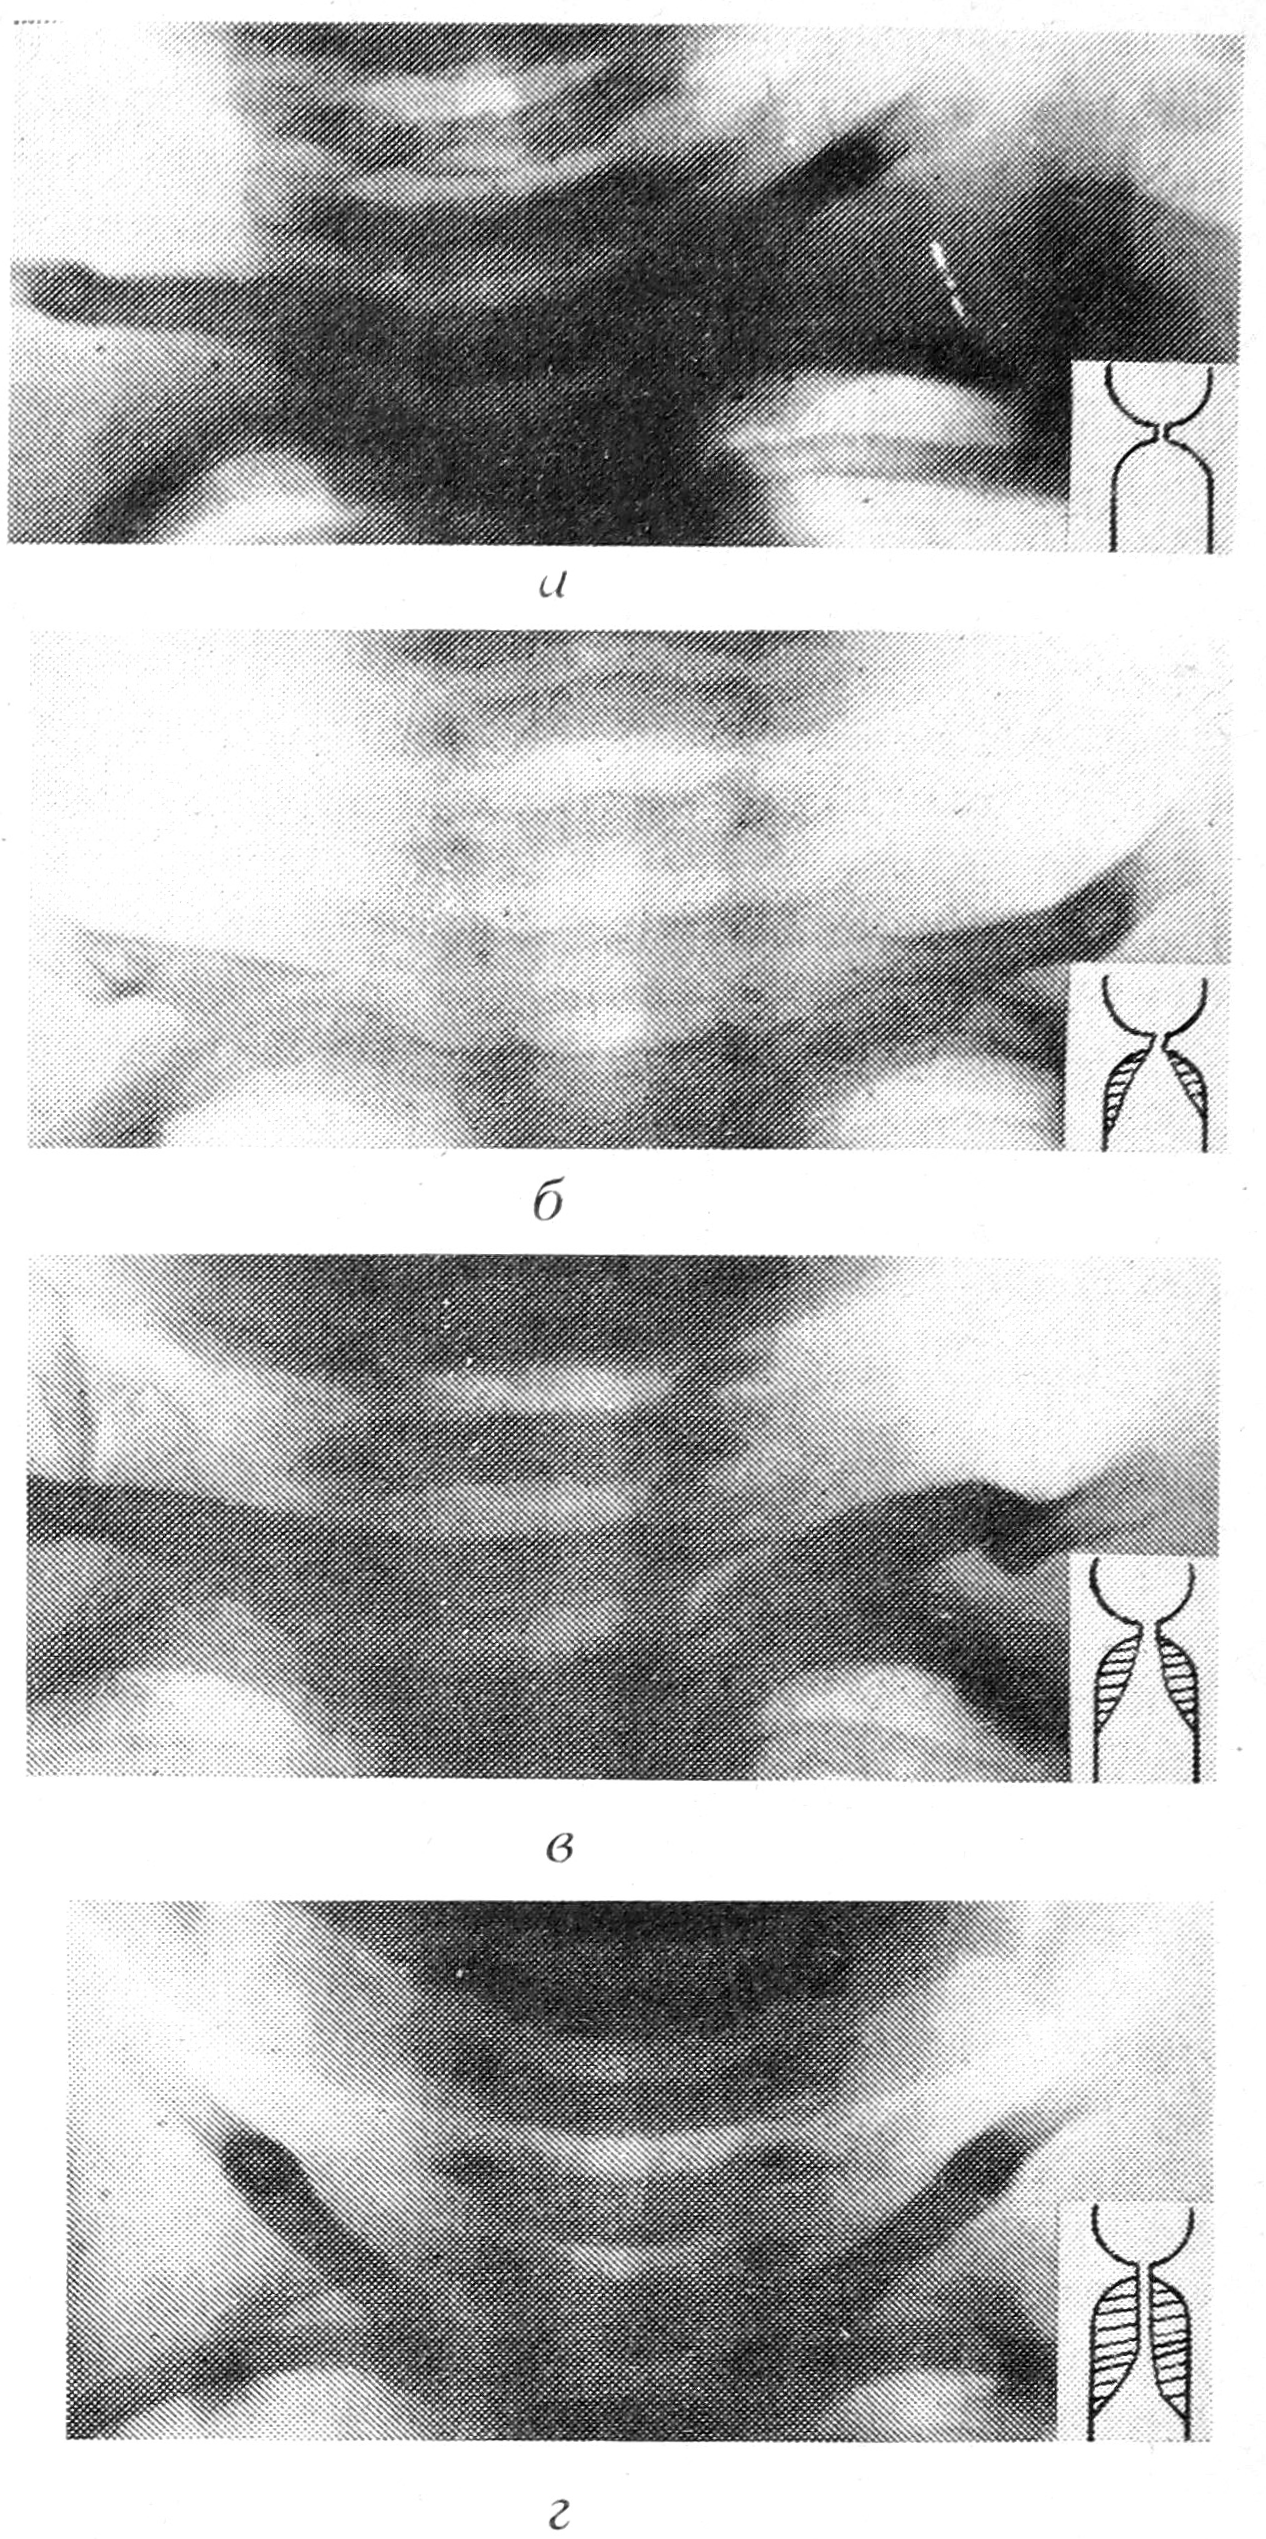

На рентгенограммах изучали состояние легких и форму воздушного столба подскладкового отдела гортани, которая в норме представляет собой куполообразное расширение с четкими контурами (рис. 1 а). При наличии отека в подскладковом отделе гортани на рентгенограмме отмечается сглаженность углов между голосовыми складками и боковыми стенками подскладкового пространства. По выраженности деформации воздушного столба все больные были распределены на 3 группы. В 1-ю группу вошли больные (118 чел.) с небольшим сужением верхушки воздушного столба в пределах 1/3 подскладкового пространства (рис. 1 б); во 2-ю (69) — с умеренным сужением в пределах 2/3 подскладкового пространства (рис. 1 в); в 3-ю (13) — с резким сужением и образованием узкого хода (рис. 1г).

Рис. 1. Рентгенограмма гортани и шейного отдела трахеи при различных стадиях стеноза: а — стеноза нет, б — стеноз I стадии, в — II стадии, г — III стадии.